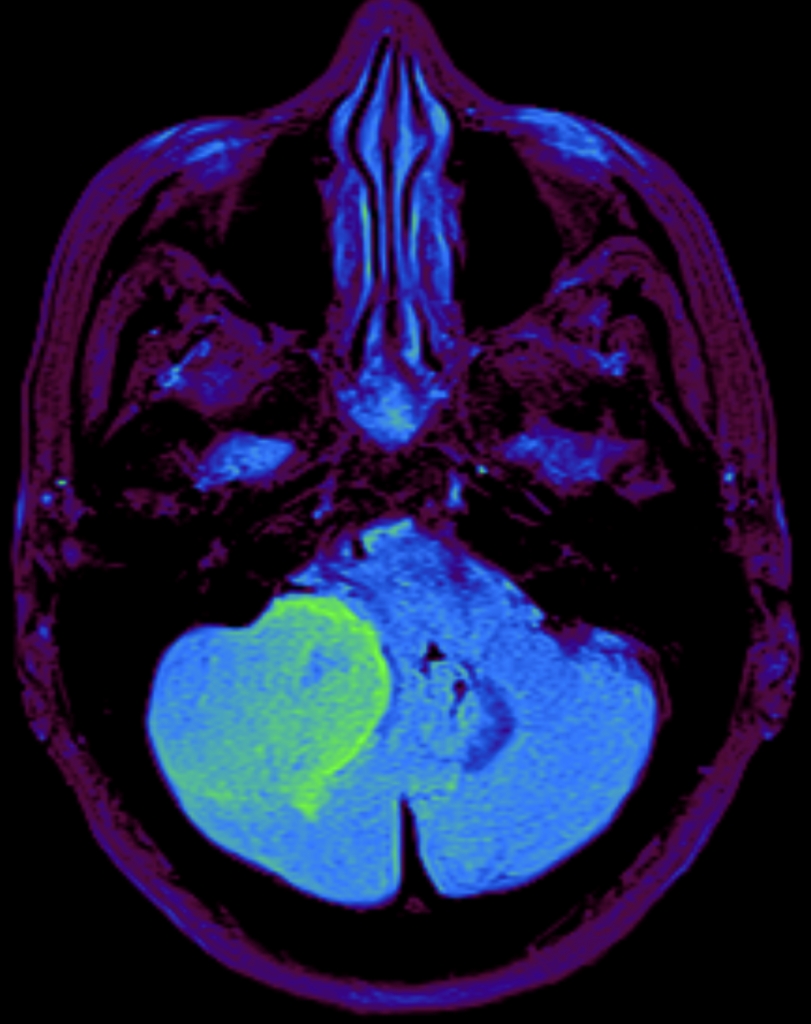

Meningioma

Los meningiomas son tumores generalmente benignos que se originan en una de las capas que forman las meninges y representan el 30% de los tumores primarios del sistema nervioso.